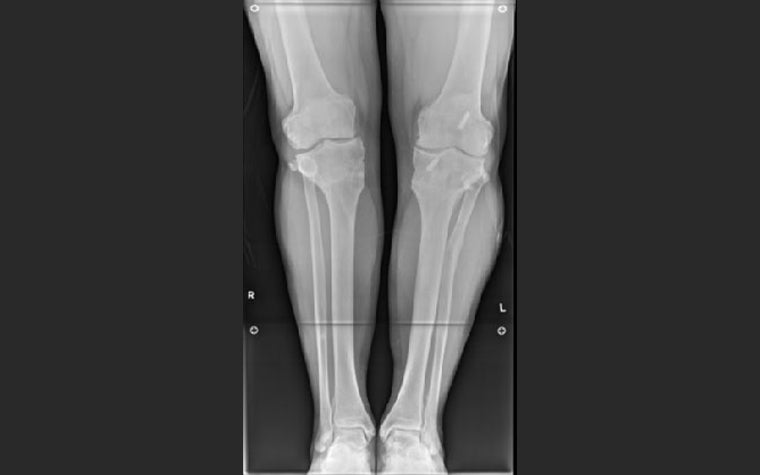

Considering the right leg first, examination of the long-leg weight-bearing AP X-ray shows good mechanical axis alignment but a significantly oblique knee joint line (figure 1). It was apparent that mild osteoarthritis had become worse over time, presumably as a result of the joint obliquity.

With the AP long-leg X-ray loaded into the OrthoView application, the surgeon used the Mechanical Axis Deviation (MAD) Wizard from the Limb Deformity Correction (LDC) Module.

This confirmed that the knee joint line convergence angle was outside of normal range. Specifically, using the nomenclature developed by Paley et al., the mLDFA (mechanical Lateral Distal Femoral Angle) and MPTA (Medial Proximal Tibial Angle) were 7.5 degrees and 10 degrees outside of normal range, respectively.

All values out of range are highlighted in red in figure 2.